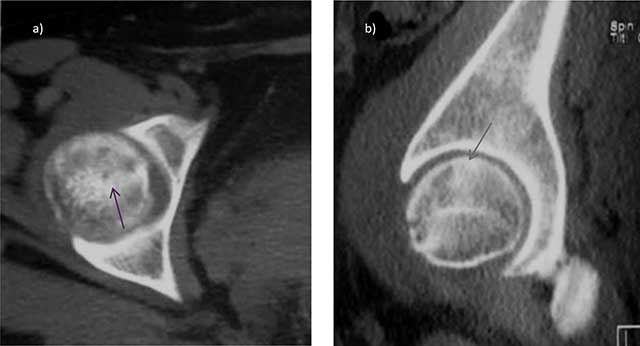

Figure 6

Stress fracture of the femoral head in the postpartum: axial a) and sagittal b) CT views show a subtle fracture line (arrows).